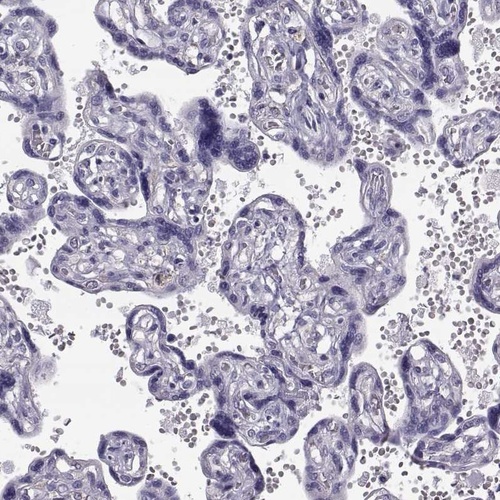

Immunohistochemistry analysis in human lymph node and placenta tissues using Anti-ADGRG5 antibody. Corresponding ADGRG5 RNA-seq data are presented for the same tissues.